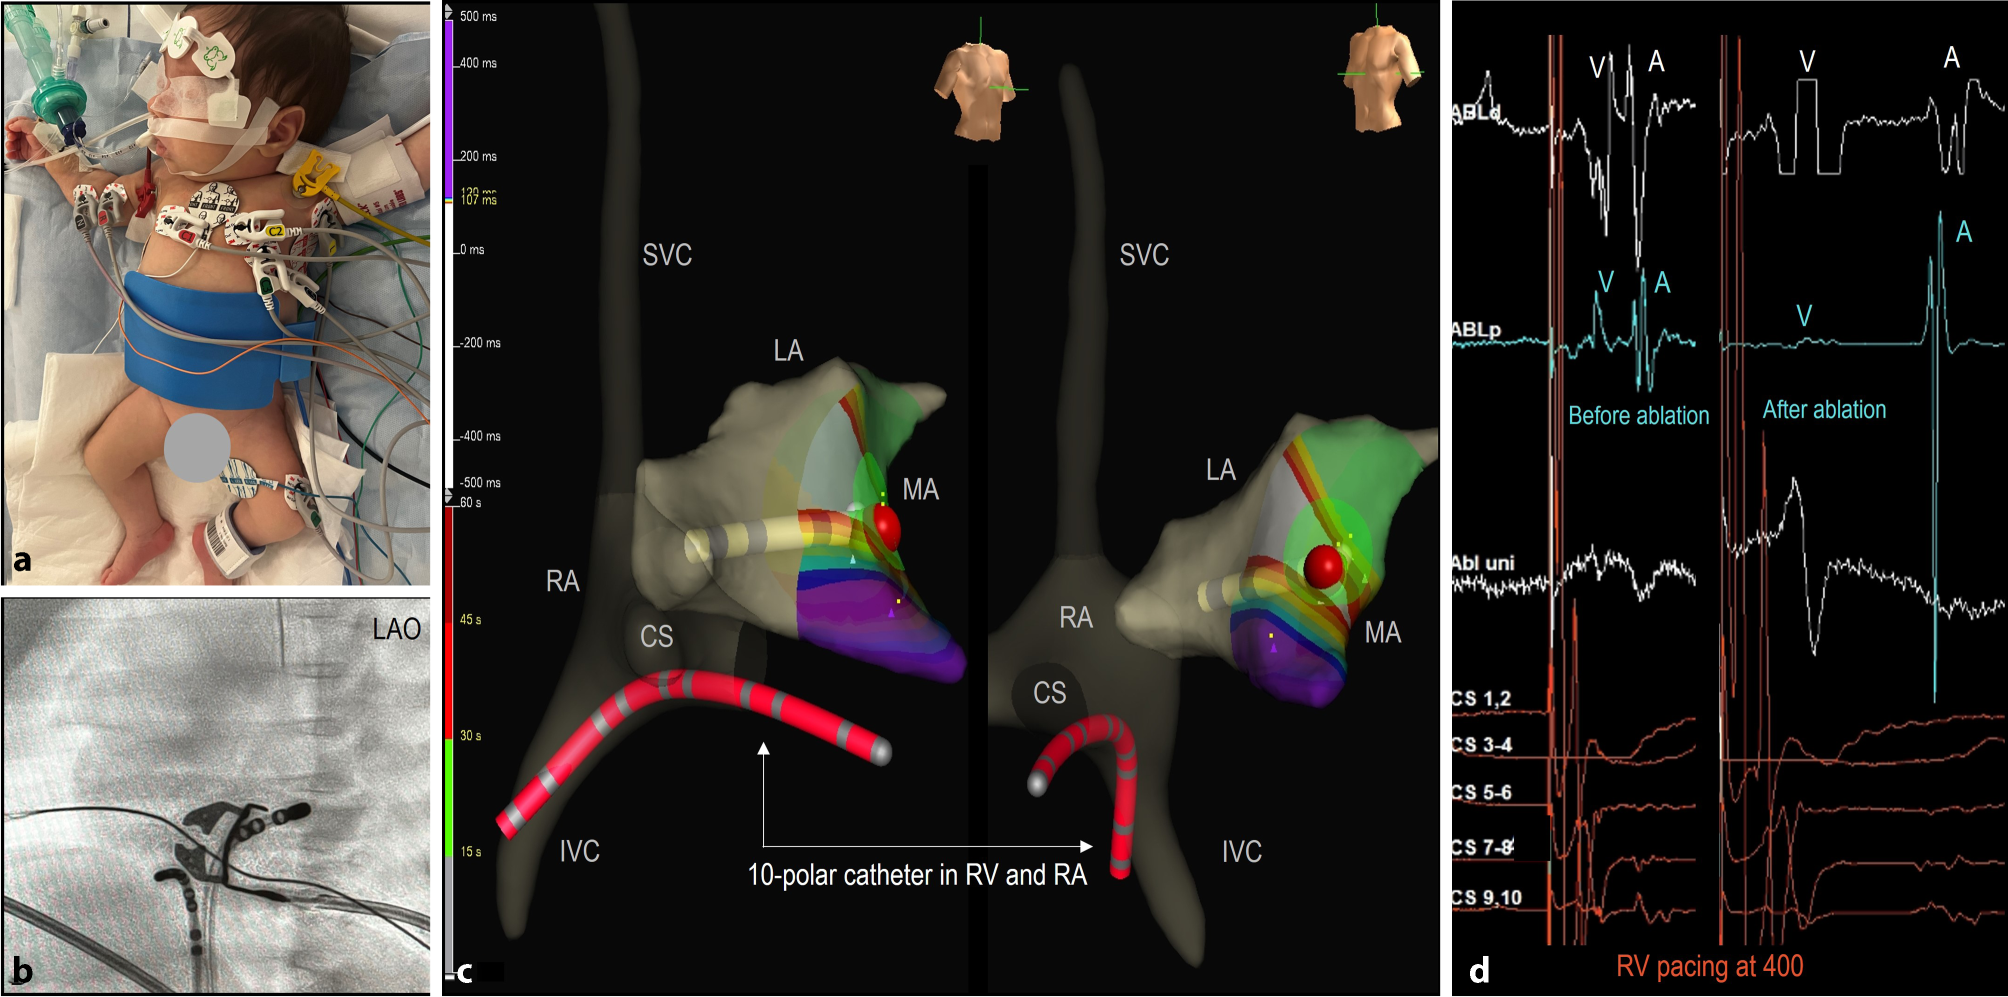

Ablation procedure

All procedures were conducted under general anaesthesia using an electroanatomic mapping (EAM) system (EnSite Precision, Abbott, St Paul, MN, USA). The surface electrodes and patches required modification to fit the infants’ torso (Fig. 1). Heparin was administered intravenously at a dose of 100 IU/kg. In most cases, a single 5 Fr ten-pole steerable catheter was used for pacing and recording of the right atrium (RA), His, and right ventricle (RV) signals (Fig. 1). Only in postoperative patient 6, two diagnostic catheters were placed in the coronary sinus and at the His position. When multiple catheters were needed, echo-guided vascular access was obtained through both femoral veins. AADs were discontinued 12 to 24 h before the procedure. Mapping was performed during SR in case of preexcitation, or during orthodromic AVRT and/or ventricular pacing. The procedural findings and techniques are summarized in Tab. 2, supplementary material.

Fig. 1

Adjustments to ablation procedures in infants. a Positioning of electrodes and patches: 3D electroanatomic system-, radiofrequency-, and ground-patches were cut to fit the infants’ torsos. b LAO fluoroscopic image of the 7 Fr RF catheter and the 5 Fr 10-pole steerable diagnostic catheter located in the RV and c 3D electroanatomical reconstruction of the right (RA) and left atria (LA) in RAO and LAO views showing the RF catheter and RF application (red dot) in the mitral annulus (MA) for a left sided concealed accessory pathway. A single 5 Fr 10-pole steerable catheter (red) was used for pacing and recording of the right atrium, His, and right ventricle (RV), reducing the number of required intracardiac catheters. d Intracardiac signals recorded during RV pacing before and after ablation, demonstrating a left-sided accessory pathway with the first atrial activation in the distal CS. Almost fused VA signals (ablation distal) were separated after ablation. A atrial, CS coronary sinus, IVC inferior vena cava, LAO left anterior oblique, RAO right anterior oblique, SVC superior vena cava, V ventricular

Patients 1 and 3 had an AVRT involving a concealed right lateral AP (Cycle length (CL) 370 ms) and an overt right posterior AP (CL 300 ms), respectively. Patients 2 and 4 both had AVRT with concealed left posterior and lateral APs (CL 270 ms, 280 ms) respectively, which were mapped through a patent foramen ovale (PFO) (Fig. 1). All four APs were successfully interrupted. However, in patient 1, accessing the right lateral AP via the inferior vena cava proved challenging, likely leading to suboptimal tissue contact and subsequent recurrence of AVRT within a few days. A second RFCA procedure from the left jugular vein resulted in improved contact and successful ablation. Similarly, patient 2 initially underwent RFCA with a 5 Fr RF catheter at relatively low power settings (20 Watts), but AVRT recurred within a week. A second RFCA using a 7 Fr RF catheter (30 Watts) provided better contact at the mitral valve annulus and was successful.